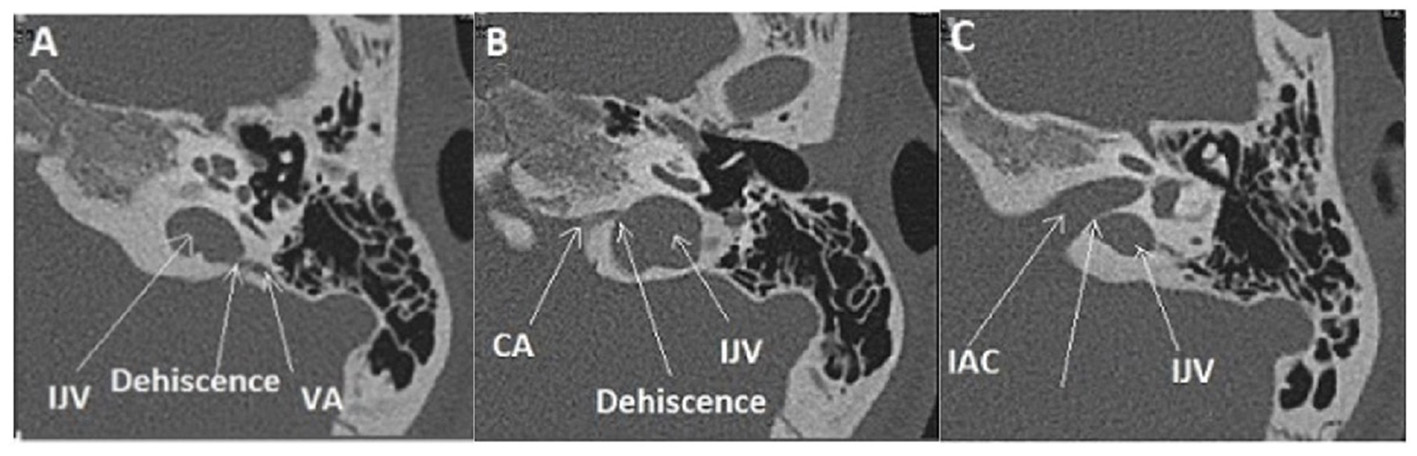

Type IIb

Concern OCD involving the internal jugular vein (IJV) and various vestibular structures.

A dehiscence involving the vestibular aqueductus (VA) in contact with the IJV (Figures 2A,B) was found in 20 ears (14 right-sided, 6 left-sided), in 19 patients (6M, 13F), aged 11–72. The presentation was bilateral in one patient (1F). A dehiscence between IJV and PSC was found in 5 temporal bones (3 right-sided, 2 left-sided) in 4 patients (4F) aged 12–50. A dehiscence concerning the IJV and the cochlear aqueductus (CA) was found in 3 ears (left-sided) in 2 patients, age varying from 12 to 53 (1M, 1F).

In this subtype, the second most prevalent in our series as it was diagnosed in 19 from 97 patients, vertigo and/or pulsatile tinnitus induced by exertion were also constantly reported. Positional vertigo was also a commonly reported symptom with no evidence for a true benign positional paroxysmal vertigo (BPPV).

Intralabyrinthine TMWA-like. (A,B) Vestibulo-vestibular dehiscence: between the vestibular aqueduct widened to 3 mm (blue arrow) and the right posterior SC (yellow arrow) at the level of the common crus (B).

Figure 5

Multiple localization OCD (case report 1): high-riding left IJV at the origin of two type II of OCD. (A) Procidence of the IJV in the IAC (White arrow), a thin bone lamina is still remaining, (B) Dehiscence between IJV interface and VA. (C) Dehiscence between IJV interface and CA. IJV, internal jugular vein; IAC, internal auditory canal; VA, vestibular aqueduct; CA, cochlear aqueduct.